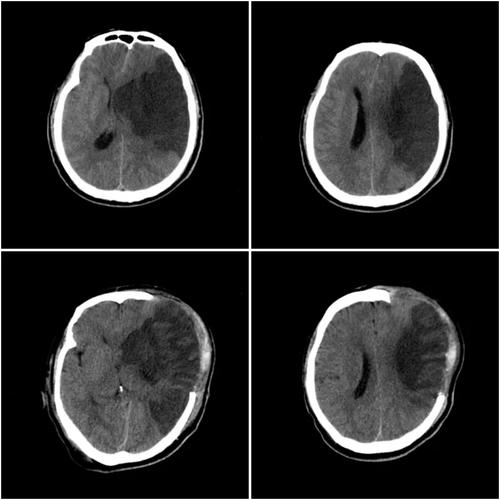

脑梗(医学上称为“缺血性脑卒中”)就是大脑的某一部分因为血管堵塞,导致血液供应中断,从而引发脑组织缺血、缺氧,最终坏死。

脑CT上显示的这个“病灶”,就是已经坏死的脑组织,CT影像上的低密度区,代表的是失去功能的脑细胞。

- 脑CT在发病早期(6小时内)可能显示不清。 在脑梗刚发生的几小时内,CT可能完全正常,或者只有细微的变化,医生通常需要结合临床症状和MRI(磁共振)来确诊。

- 当CT明确显示出了梗塞灶时,通常意味着梗塞已经发生了一段时间(一般超过6-24小时),坏死的脑组织已经形成。